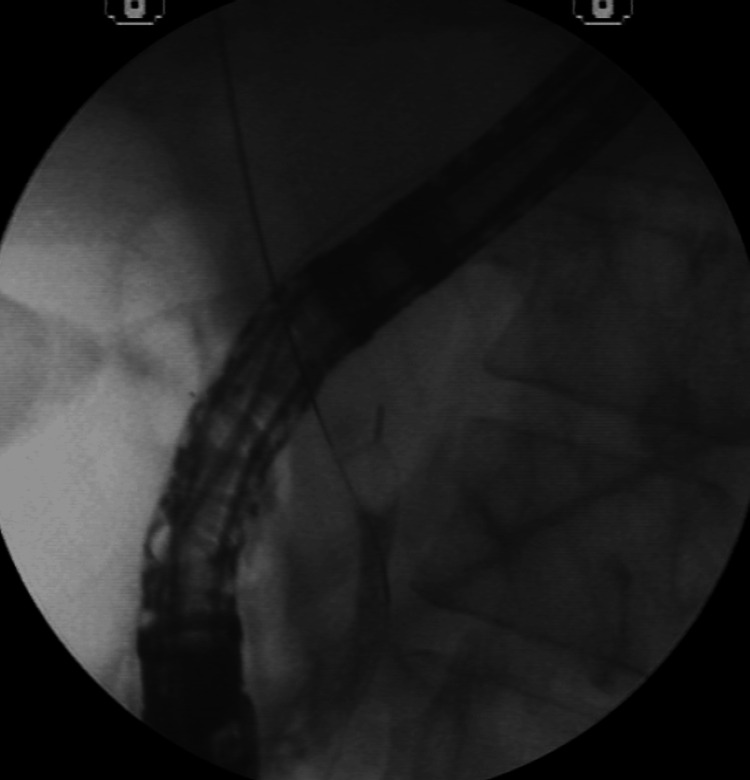

Basket passage and stone capture for attempted removal; however, distal CBD narrowing did not allow the set to be removed. Mechanical lithotripsy was performed in an attempt to fragment the stone (Figure 7).

Mechanical lithotripsy was unsuccessful in fragmenting the stone, and a complication arose when the proximal rod of the basket broke, making it challenging to remove the basket along with the trapped stone (Figure 8).

A second 15-mm dilation was performed to remove the imprisoned basket along with the calculi (Figure 9).